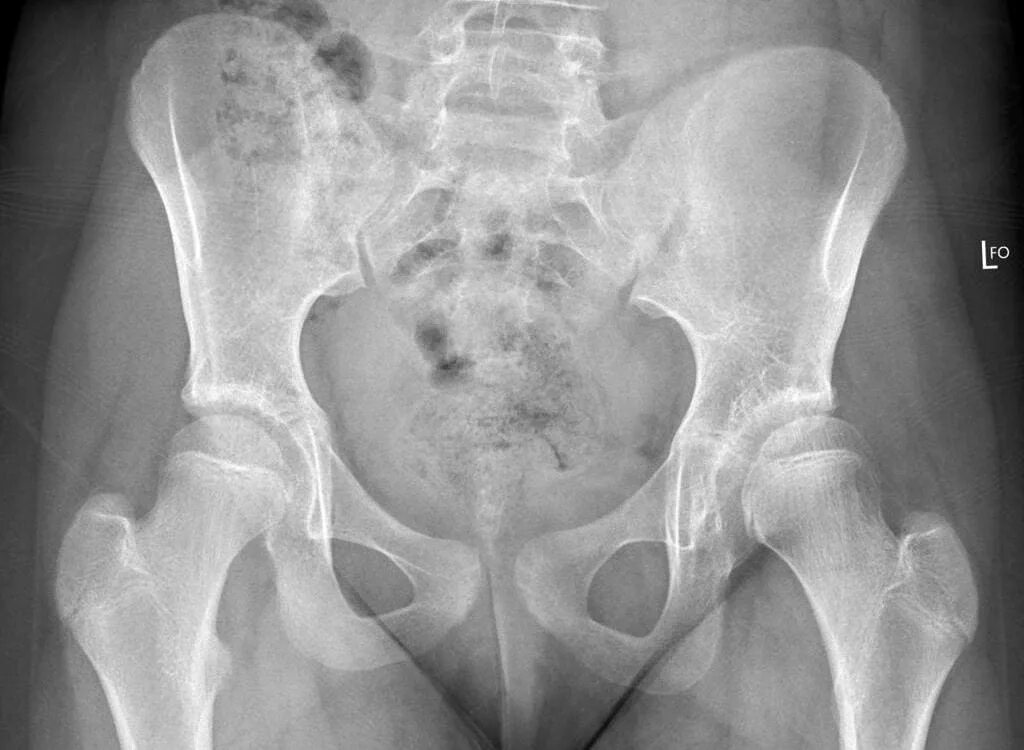

Дисплазия 7 лет